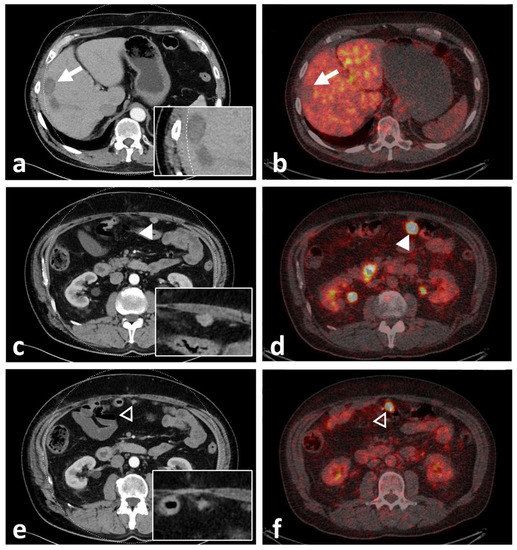

Figure 6. Computed tomography (CT) with inserted magnifications (left) and axial fused PET/CT images (right) of participant 9, demonstrating lack of uptake of 68Ga-NeoBOMB1 in a mildly enhancing liver metastasis (white arrow, (a,b)) and two omental metastases with significant tracer uptake (c,d) [white arrowhead] and (e,f) [black arrowhead]). The latter lesion was missed upon initial staging by CT.

Even though physiological 68Ga-NeoBOMB1 organ distribution was uniform in all participants with strong uptake mainly in the pancreas and urinary system [25], tumor uptake varied. Tracer accumulation in all lesions was shown in 33.3% (n = 3) of participants: 33.3% (n = 3) showed tracer accumulation only in a subset of lesions; and 33.3% (n = 3) showed no increased uptake in tumor lesions identified on CT (please also refer to the illustrative Figure 5). In three participants, a mixed uptake—i.e., a subset of lesions with no tracer uptake in the presence of other lesions with tracer uptake—were observed (Figure 6). On a per-lesion basis, 17 of 37 lesions (45.9%) were detected by 68Ga-NeoBOMB1, whereas 16 lesions (54.1%) were negative on 68Ga-NeoBOMB1 PET, explained in part by a significantly lower tracer uptake in lesions with necrotic CT appearance. On the other hand, five lesions (13.5%) could only be identified via 68Ga-NeoBOMB1-PET and were not initially evident on CT. Although the current gold standard for staging GIST is still contrast-based CT including Choi-criteria to report on vitality [26], the decision was made early on to include all GIST lesions found with either CT, 68Ga-NeoBOMB1-PET, or a combination of both methods to define the overall disease burden most accurately. Overall, we could corroborate study findings by Dimitrakopoulou-Strauss et al. in patients with GIST using 68Ga-BZH3, that also showed variable uptake in only seven out of 17 patients and eight out of 30 lesions [14].